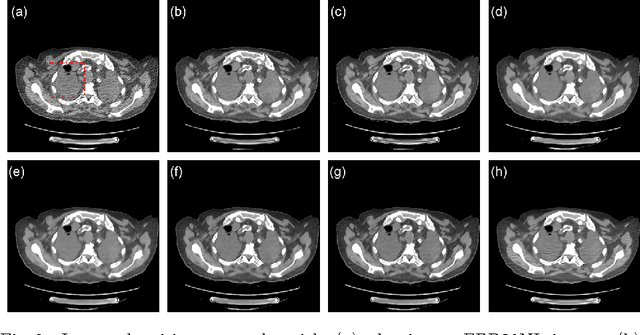

Increasing use of CT in modern medical practice has raised concerns over associated radiation dose. Reduction of radiation dose associated with CT can increase noise and artifacts, which can adversely affect diagnostic confidence. Denoising of low-dose CT images on the other hand can help improve diagnostic confidence, which however is a challenging problem due to its ill-posed nature, since one noisy image patch may correspond to many different output patches. In the past decade, machine learning based approaches have made quite impressive progress in this direction. However, most of those methods, including the recently popularized deep learning techniques, aim for minimizing mean-squared-error (MSE) between a denoised CT image and the ground truth, which results in losing important structural details due to over-smoothing, although the PSNR based performance measure looks great. In this work, we introduce a new perceptual similarity measure as the objective function for a deep convolutional neural network to facilitate CT image denoising. Instead of directly computing MSE for pixel-to-pixel intensity loss, we compare the perceptual features of a denoised output against those of the ground truth in a feature space. Therefore, our proposed method is capable of not only reducing the image noise levels, but also keeping the critical structural information at the same time. Promising results have been obtained in our experiments with a large number of CT images.